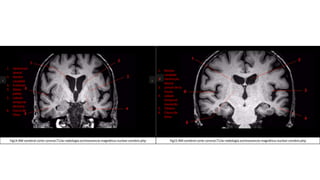

TAC de infarto en los ganglios de la base

RM de infarto cerebral en el territorio de

la arteria cerebral media